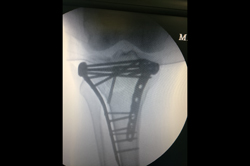

Proximal Tibia